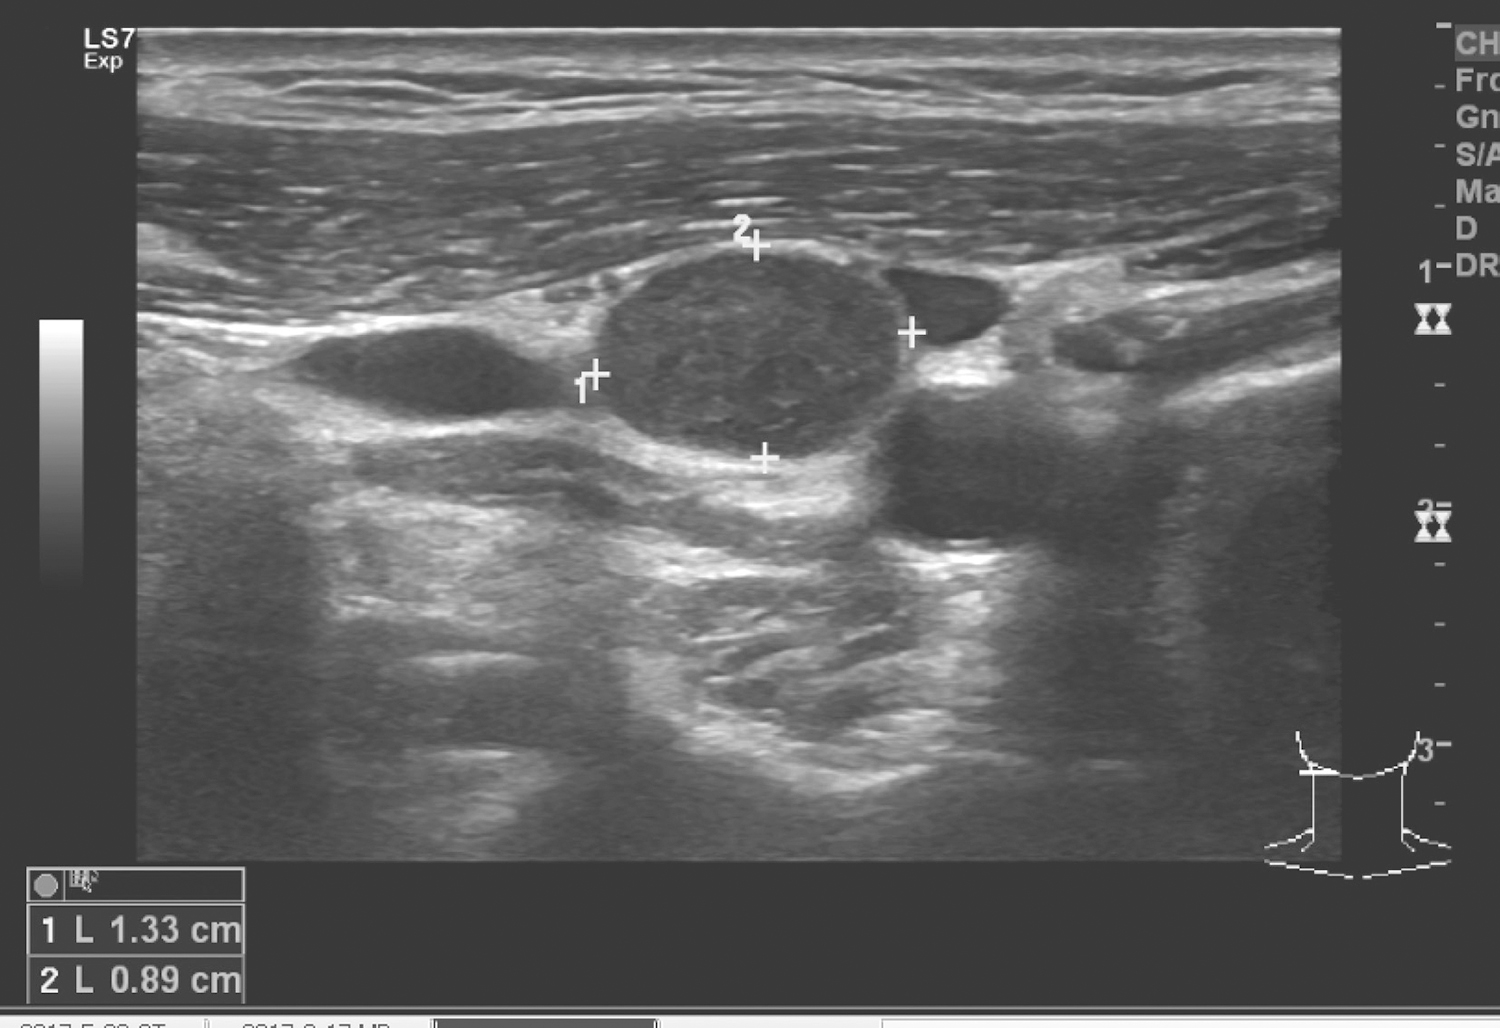

4.2017年3月16日颈部B超

右颈Ⅱ区可见一低回声结节,约1.3cm×0.9cm,边界清楚,未见血流信号(图6)。余颈部及锁骨上未见明确肿大淋巴结。

图6右颈部Ⅱ区见低回声结节

超声诊断:右颈Ⅱ区淋巴结转移。